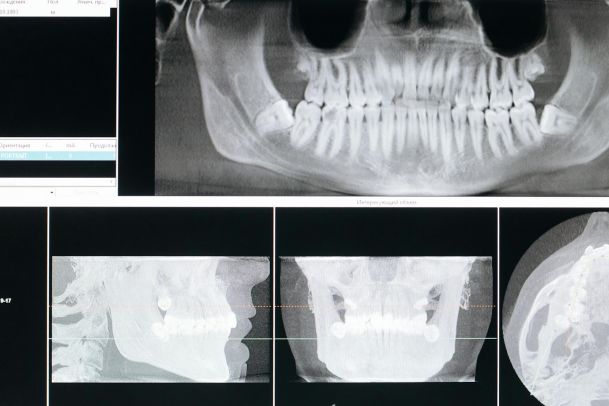

Ортопантомограмма

Метод ортопантомографии (ОПТГ) — расширенная версия рентгена. В этом случае снимают не конкретный зуб, а обе челюсти в панорамном формате. Видны костные и мягкие ткани, хорошо просматривается корневая структура, пародонт, синусы. Метод показывает, где именно развивается кариес и прогрессирует воспаление.

Панорамный снимок делают после травмы челюсти, перед установкой брекетов, съемным протезированием. На это исследование направляют перед удалением корней, диагностикой кист, опухолей, гнойников или лечением заболеваний пародонта. Обследование также назначают, если причина зубной боли неизвестна.

Компьютерная томография

Результаты компьютерной томографии более информативны, чем при панорамном снимке. Исследование занимает всего несколько секунд. За это время аппарат делает множество снимков с различных ракурсов. Программа их обрабатывает и создает трехмерную модель жевательной системы. КТ позволяет увидеть состояние каналов и обнаружить стоматологические заболевания.